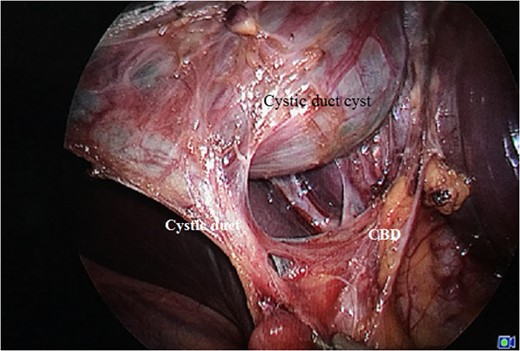

Laparoscopic view showing Calot's triangle dissected with choledochal cyst seen separately from the rest of the GB.

Cyst seen along with the cystic duct stalk and the arterial twig supplying the cystic duct.